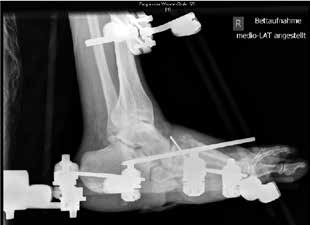

Der operative Zugang erfolgt abhängig von der Lokalisation der Charcot-Arthropathie. Bei ausgeprägten Deformitäten ziehen die Verfasser einen bilateralen Zugang vor. Neben einer sorgfältigen Entfernung avitalen Knochengewebes erfolgt gegebenenfalls eine Resektion infizierten Gewebes sowie eine Abtragung von Pseudoexostosen. Die alleinige Abtragung von Pseudoexostosen kann in einigen Fällen als alleinige operative Behandlungsmethode ausreichend sein. Bei vorhandenen Ulzera bzw. Infektionen werden gentamicinhaltige Antibiotikaträger appliziert. Autologe Spongiosa bzw. Knochenersatzstoffe können in die restlichen Defekte nach Reposition und Anfrischung der Gelenkpartner interponiert werden. Fixateur-Pins mit zentralem Gwinde werden in die Metatarsaliaköpfchenreihe, den Calcaneus und die Tibia eingebracht. Nach Reposition des Fußes wird der Fixateur externe montiert, in der Klinik der Verfasser der Hoffmann-II-Fixateur als bilaterale Rahmenkonstruktion (Abb. 4). Zielvorgabe für die dreidimensionale Stellungskorrektur ist hierbei die lotgerechte Einstellung des Fußes in der frontalen Ebene mit plantigrader Belastbarkeit (Abb. 5a u. b). Während der Tragedauer des Fixateurs erfolgt eine vollständige Entlastung der betroffenen Extremität. Der Patient ist für diese Zeit im Rollstuhl oder bestenfalls an Unterarmgehstützen mobilisiert. Sechs bis zwölf Wochen postoperativ wird das Material entfernt. Die vollständige Materialentfernung kann ohne Narkose unter Analgesie durchgeführt werden. Bis zur Versorgung mit einer Orthese wird der Fuß vor der Überbelastung des reponierten Fußes mit einem Cast geschützt.